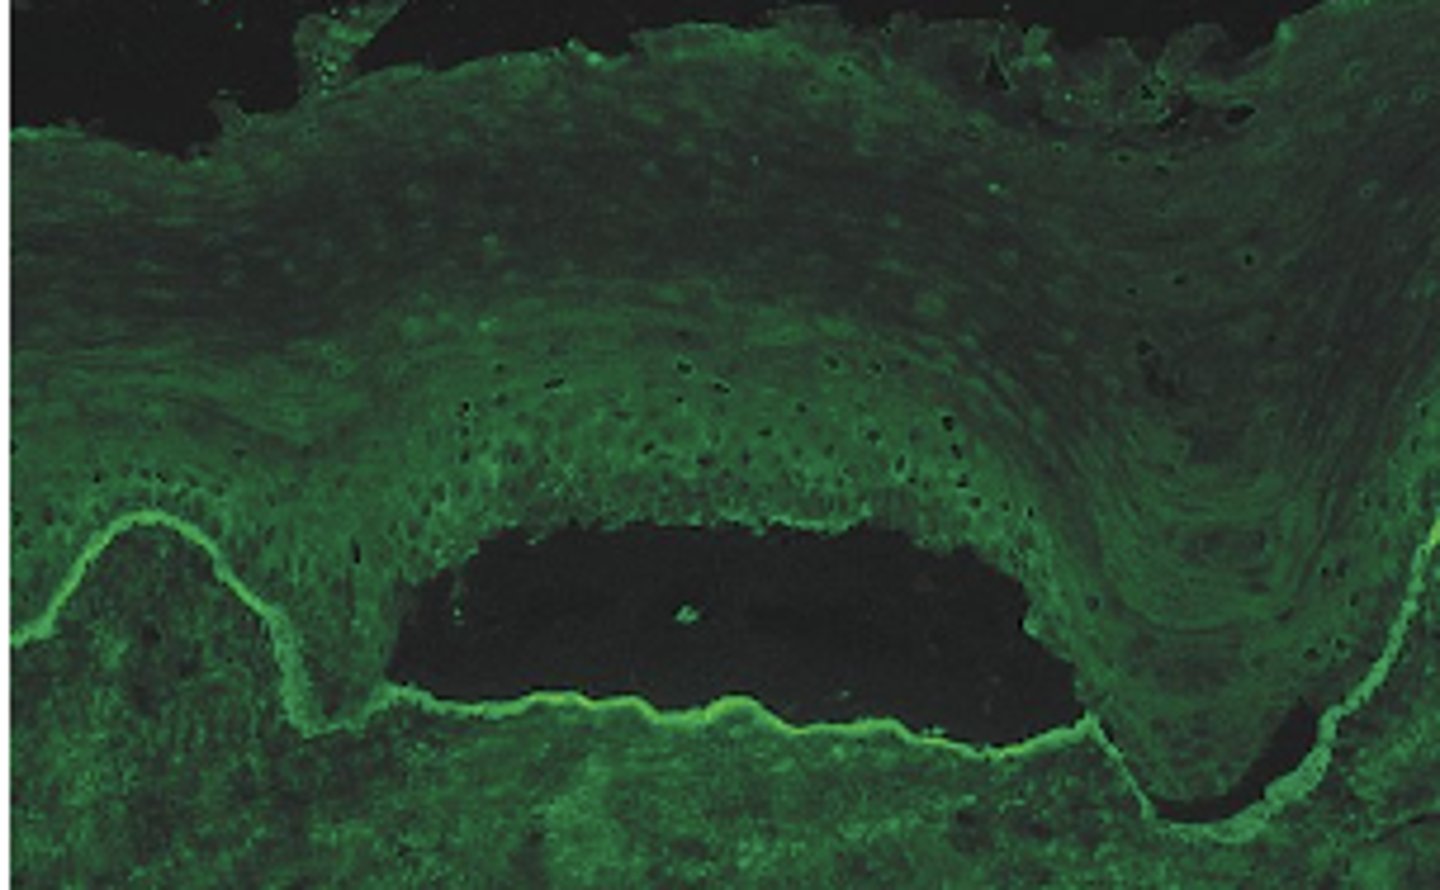

desmosomes (Pemphigus vulgaris disrupts...)

Blistering in this disease is due to antibodies directed against component of ___? (picture showing histo slide with intraepithelial split)

prickle cell layer (clear fluid blisters)

What cell layer is affected in pemphgUs (PICTURE ON DRIVE)?

hemidesmosomes

Blistering in this disease is due to antibodies directed against component of ___? (picture showing histo slide with basement layer split)